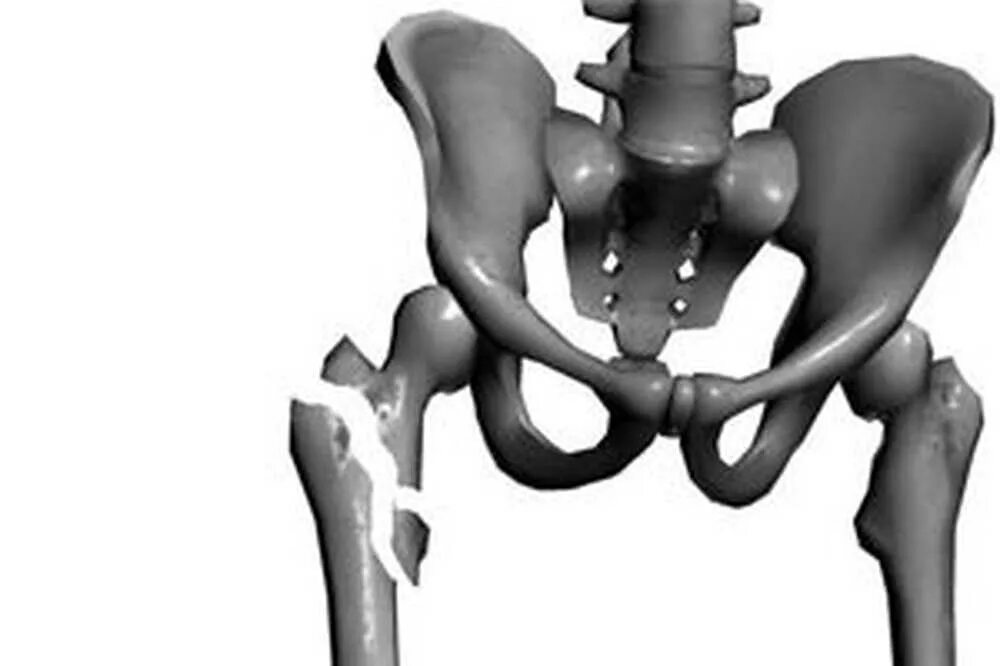

Перелом шейки бедра мкб 10 у взрослых